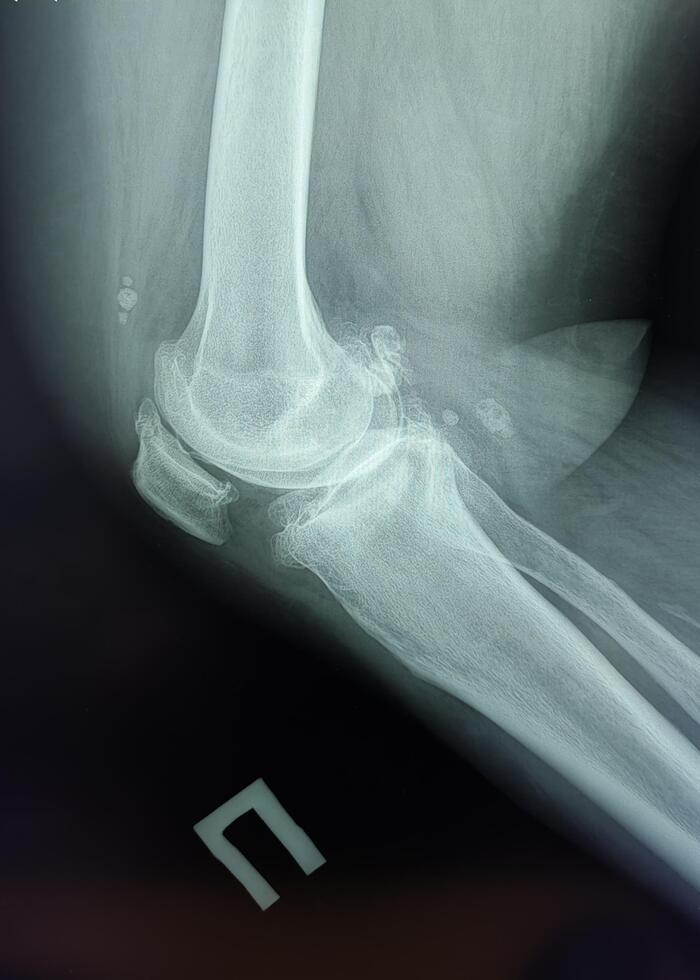

Хондроматоз – это патологическое изменение сустава, причиной которого становится перерождение синовиальной оболочки в хрящ. Это заболевание довольно редкое, может поражать любой сустав, но чаще всего страдает именно коленный сустав. Заболевание характерно для спортсменов и людей, подвергающихся регулярным тяжелым физическим нагрузкам, четкая причина возникновения неизвестна. Симптомы- боль, хруст и заклинивание сустава.

Описание: На Р-граммах правого к/с в 2х проекциях: Значительное сужение суставной щели в медиальных отделах до 1.6 мм, субхондральный склероз, краевые костные разрастания, заострение полюсов надколенника, уплотнение его внутренней поверхности ,по ходу внутренней поверхности синовиальной оболочки визуализируются единичные округлые хондроматозные тела №~7,размером от 5 мм до 25 мм в диаметре. Заключение: Хондроматоз правого коленного сустава. Гонартроз справа 3 ст. по Kellgren.Пателло-феморальный артроз.

Сами хондроматозные тела.

Лечение оперативное: артроскопическое удаление хондроматозных тел.